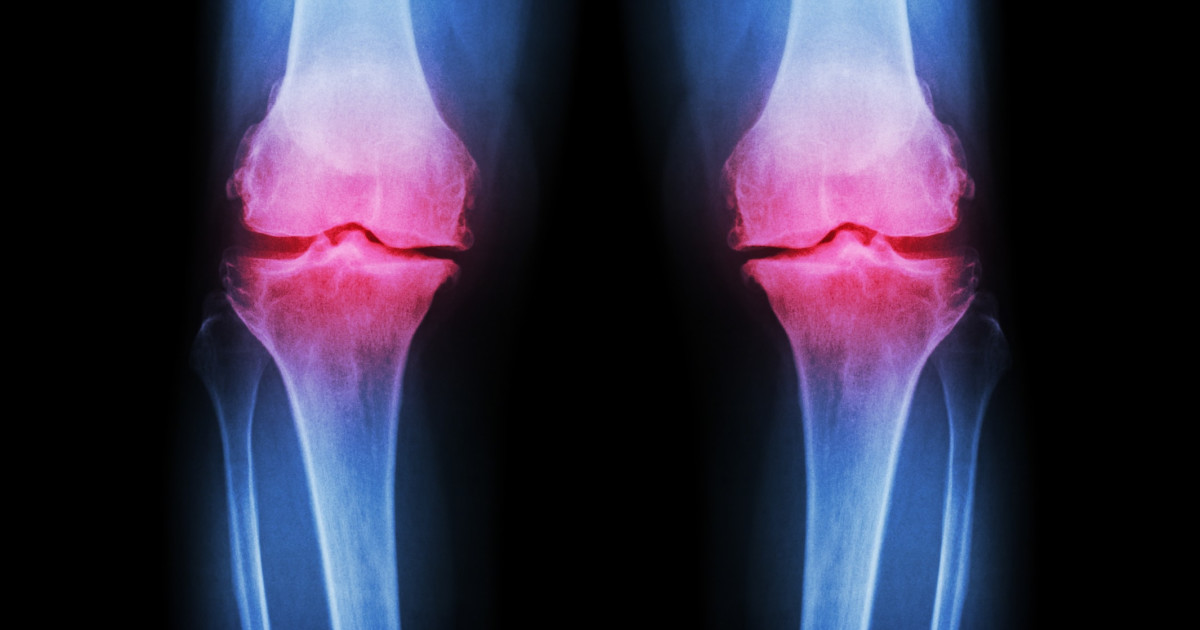

Septic arthritis is a painful joint infection that occurs when germs travel through the bloodstream from other parts of the body and settle in the joint, or when a deep injury delivers germs directly to the joint. Older adults and infants are at a higher risk of developing septic arthritis. It's most common for knees to be affected, but the shoulders, hips, and other joints can also be infected. Left untreated, septic arthritis can cause fast and severe damage to the bone and cartilage inside the joint. Treatment is done by draining the joint through surgery or a needle. A course of antibiotics might also help treat the infection. There are a number of causes and risk factors regarding septic arthritis. Uncover the details about them now.

Septic arthritis can develop because of various types of infections, including fungal, viral, and bacterial infections. Staph infections, a common bacterial infection, are most often cited as the cause. These infections are unusually common because the bacteria can live and survive on both healthy and infected skin, so individuals are at risk of developing an infection regardless of their overall health. Usually, septic arthritis develops when infections from elsewhere in the body spread via the bloodstream, lodging in the joint. These might include common infections like urinary tract infections or skin infections. Joints are lined by a material called synovium, which isn't designed to protect itself against infections. Since the joint is so susceptible to infection, the body responds with an inflammatory and strong immune response that contributes to the joint damage through increased pressure and swelling.

Osteoarthritis is just one of several conditions that can increase an individual's risk of developing septic arthritis. When a patient already has problems with their joints, the joints are more susceptible to infection due to weakness and prior damage. Chronic joint conditions like osteoarthritis, lupus, and gout are often seen alongside septic arthritis cases. Osteoarthritis most commonly affects the joints in an individual's spine, hips, hands, and knees, though it is possible for any joint to be affected. Typically, symptoms include joint stiffness, pain, and tenderness, as well as a grating sensation when the affected joint is used, a loss of flexibility in the joint, as well as bone spurs. It is crucial for osteoarthritis patients to receive appropriate and prompt treatment in order to mitigate the potential for septic arthritis to develop.